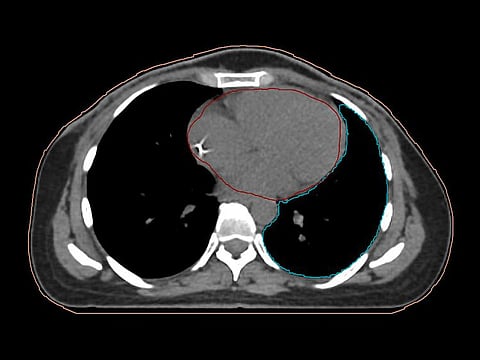

Deep Inspiration Breath Hold (DIBH) is a radiation therapy technique when patients take deep breaths and hold their breath during treatment while the radiation is being delivered. By taking deep breaths the lungs fill with air and the heart is pushed posteriorly and inferiorly away from the chest wall. This will reduce the dose to the heart and to the left anterior descending coronary artery (LDA) by nearly 50 per cent as compared with free breathing (FB) technique. There is significant decreased dose to ipsilateral lung and substantially increase in ipsilateral lung volume. The dose to the contralateral breast showed no difference between FB and DIBH.